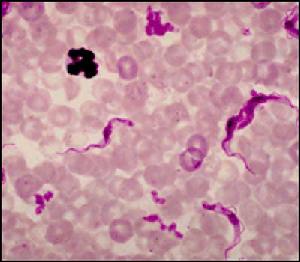

布氏錐蟲在自然感染的脊椎動物宿主體內是一種多形的蟲體,在血液中可見到沒有鞭毛的短粗型和具有鞭毛的細長型以及過渡型。因此蟲體的大小不一致,長度介於12~35um,寬度介於1.5~3.5um、錐蟲體扁無色。體形似葉,前端逐漸變為細尖,後端較圓。在體中部或中部附近,有1較大的核;近後端有1扁圓形的動基體。蟲體的一側有寬而呈波浪狀的波動膜,有1根鞭毛自毛基體發出,沿波動膜的邊緣向前延伸,在前端伸出,成游離的鞭毛。錐蟲很活潑,借鞭毛和波動膜運動。錐蟲借縱分裂繁殖,在塗片檢查時可見到正在分裂的蟲體。

布氏錐蟲的血液塗片自然感染病例的潛伏期約為10天。馬屬動物發病時體溫迅速升高至40~41℃ ,患畜精神不振,食慾下降,脈搏快而弱;結膜潮紅,結膜有時雜有小出血,眼中流淚;鼻孔中流出漿性鼻液;四肢、腹下、外陰部周圍、喉部和眼瞼發生界限明顯的水腫。

(2)病原學檢查。取病畜1滴血液加等量生理鹽水直接在顯微鏡下檢查。也可取病畜血液、淋巴液、腦脊液後骨髓穿刺液作塗片鏡檢。患畜在發熱期間常能在外周血液中查到蟲體。